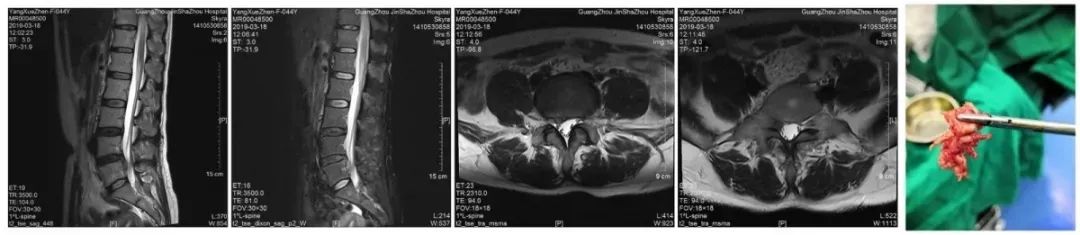

外科治疗

研究中对临床治愈的病人,做脊椎X线、CT、MRI复查,可见椎体和关节的排列、椎管矢状径、椎间孔变窄已恢复到代偿范围或正常范围,而椎间盘膨出、突出、韧带钙化和骨质增生基本上与发病期无明显改变,这证明疗效主要来源于恢复椎管、椎间孔的正常位置和代偿空间。

而对于脊椎椎管、椎间孔位置不正确,失去了代偿空间,脊髓及神经根无可逃逸的空间,仍采用保守治疗,效果欠佳,治疗是徒劳的!

而需要借助外科手术,才能解决椎间盘突出物与脊髓、神经的空间位置问题才能根本上解决问题。至于选择哪一种治疗方式,会有什么样的治疗效果,当然要咨询临床经验丰富的专科医师,获取良好治疗效果。